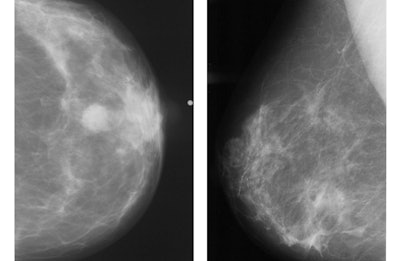

Abnormal mammogram, left. Normal mammogram, right. Images and caption courtesy of RSNA.

Women who attended all their invited screening mammograms had a survivability rate of over 80%, while those who didn’t participate in any screenings had a survival rate that ranged from 59.1% to 77.6%, Smith’s team noted. Further, women who attended all five screening mammograms saw a 72% reduction in the risk of dying from breast cancer compared with women who didn’t participate in any screening mammograms.